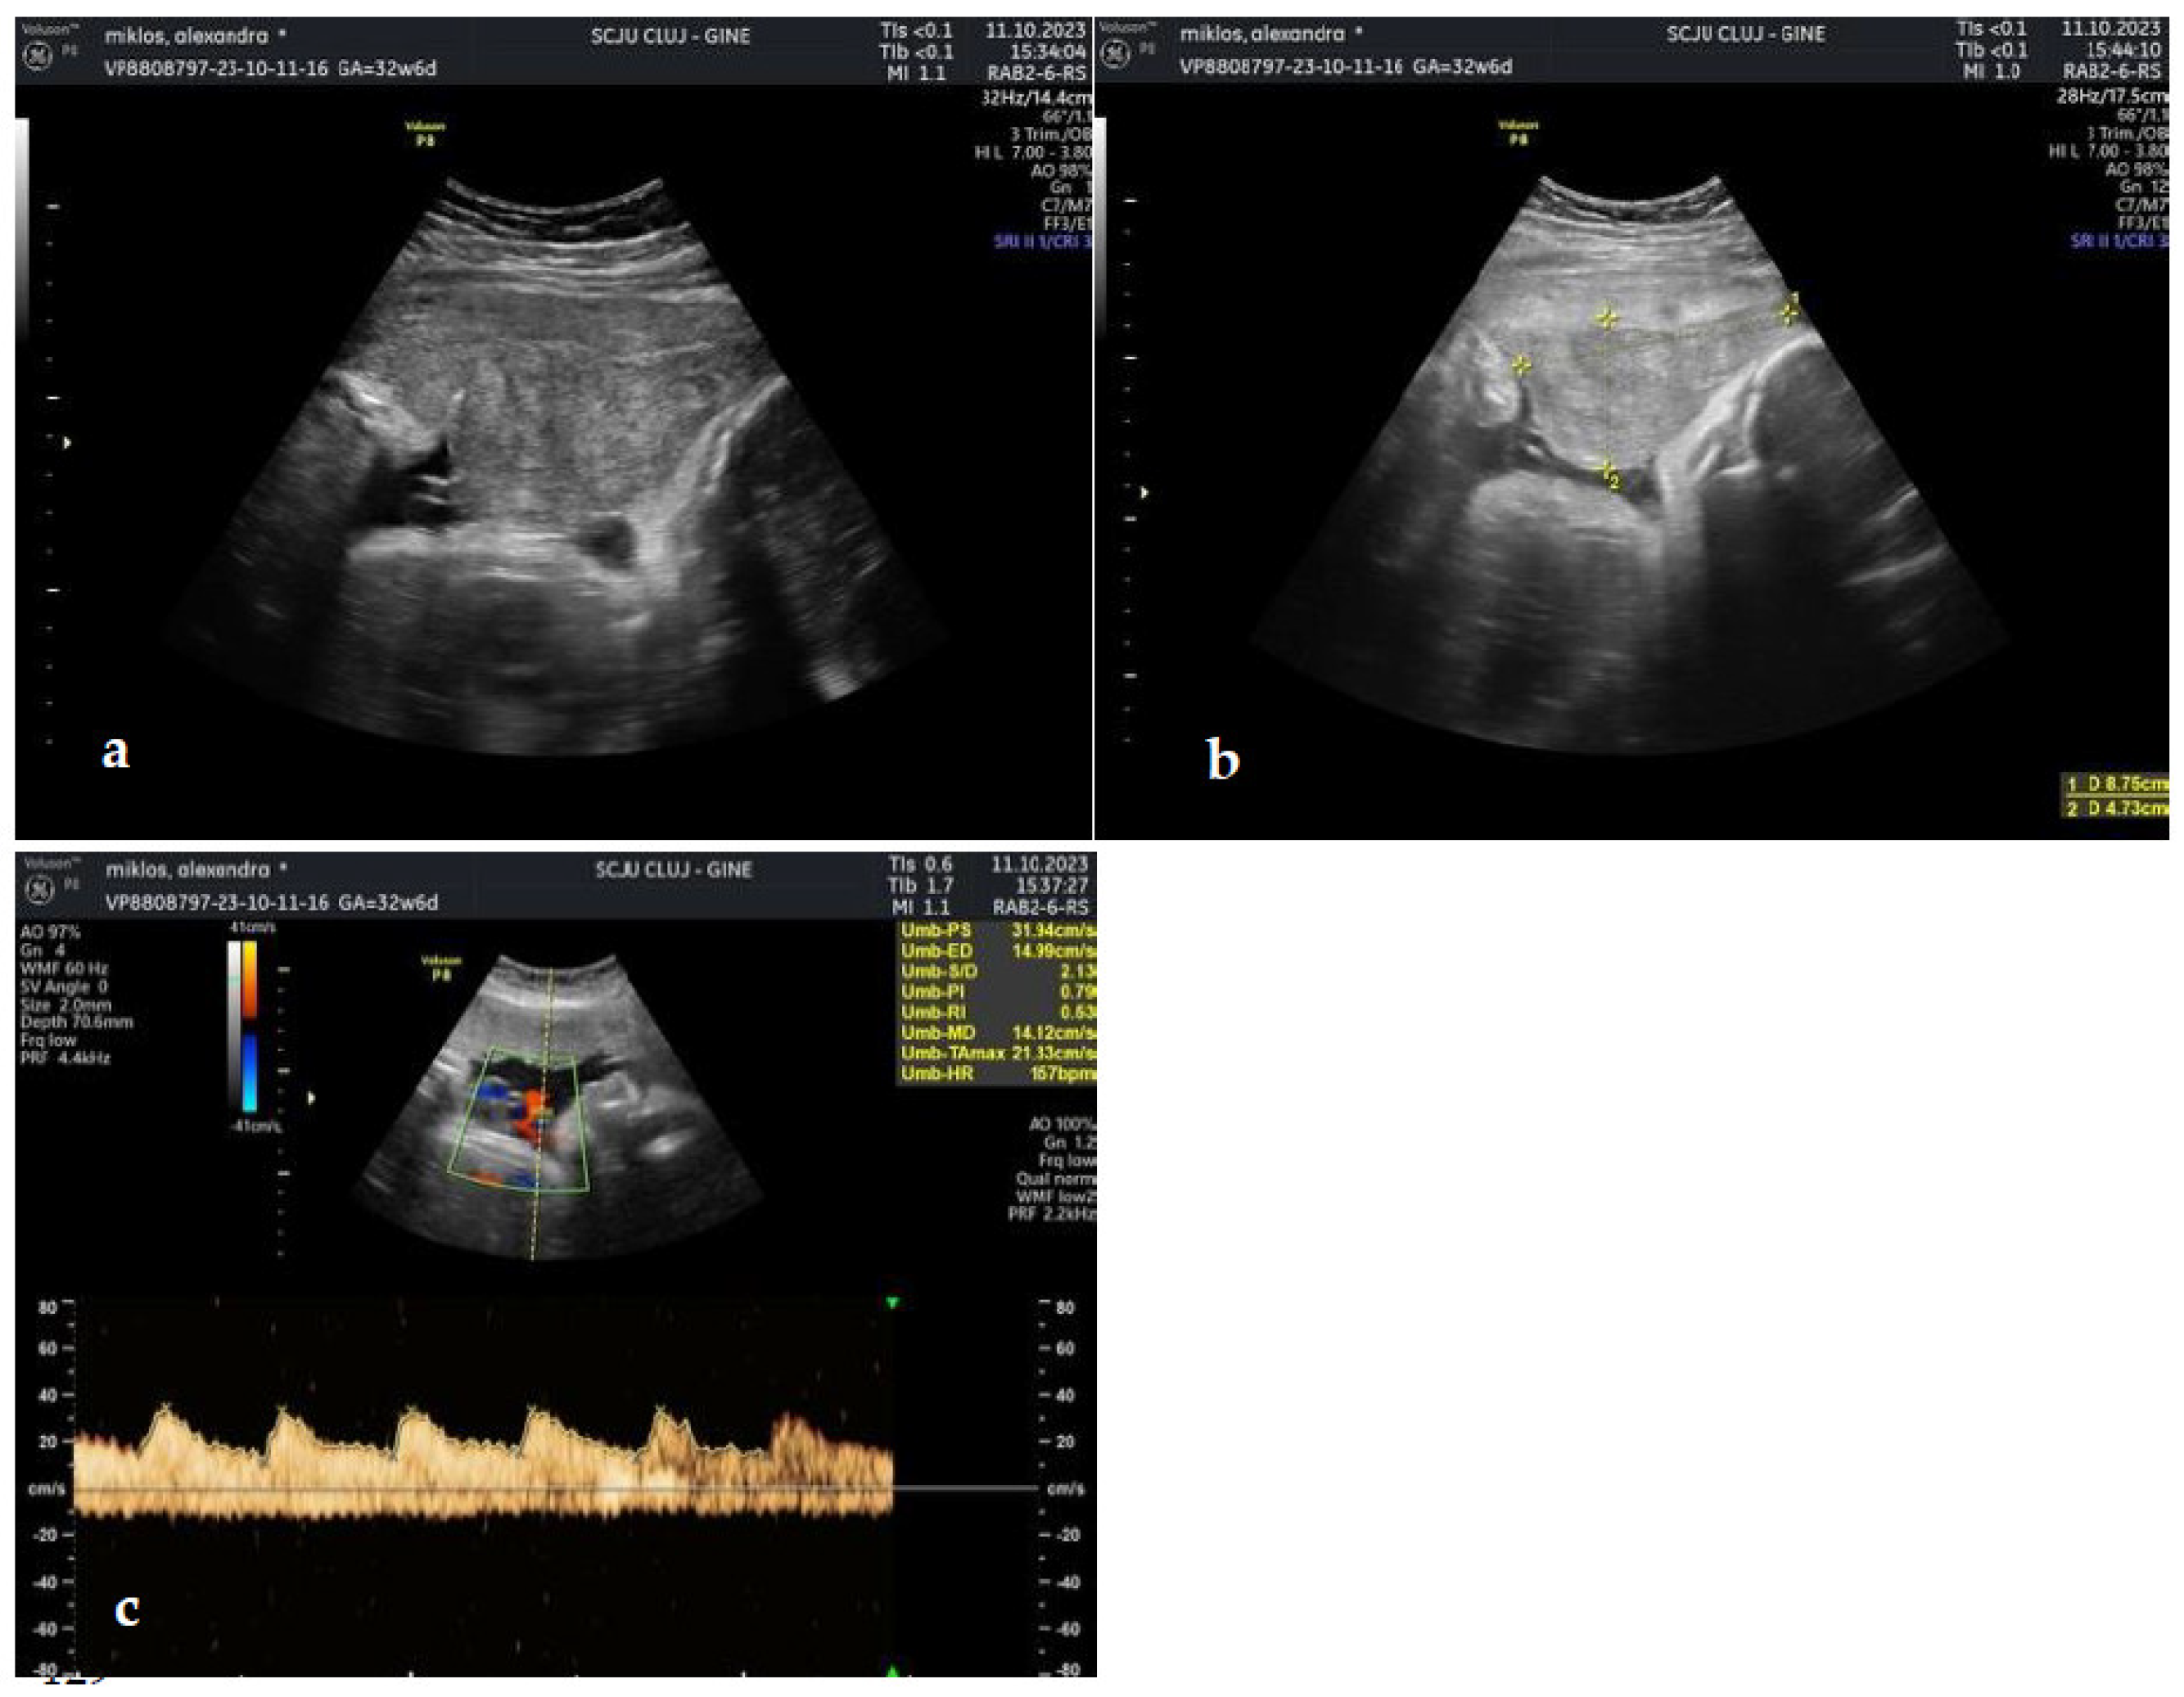

The patient presented to the emergency room at 33 WG with moderate vaginal bleeding, which had initiated approximately 40 minutes prior to arrival, without uterine contractility and normal fetal movements. The clinical examination confirmed moderate vaginal bleeding, without cervical changes. The patient was normotensive (no history of hypertension during pregnancy), with mild tachycardia. Ultrasound scanning identified a retroplacental hematoma of approximately 9/5 cm with normal fetal heart rate, and normal Doppler indices (Figure 3).

Figure 3. (a,b). Retroplacental hematoma (c). Normal doppler parameters measured on the umbilical artery.